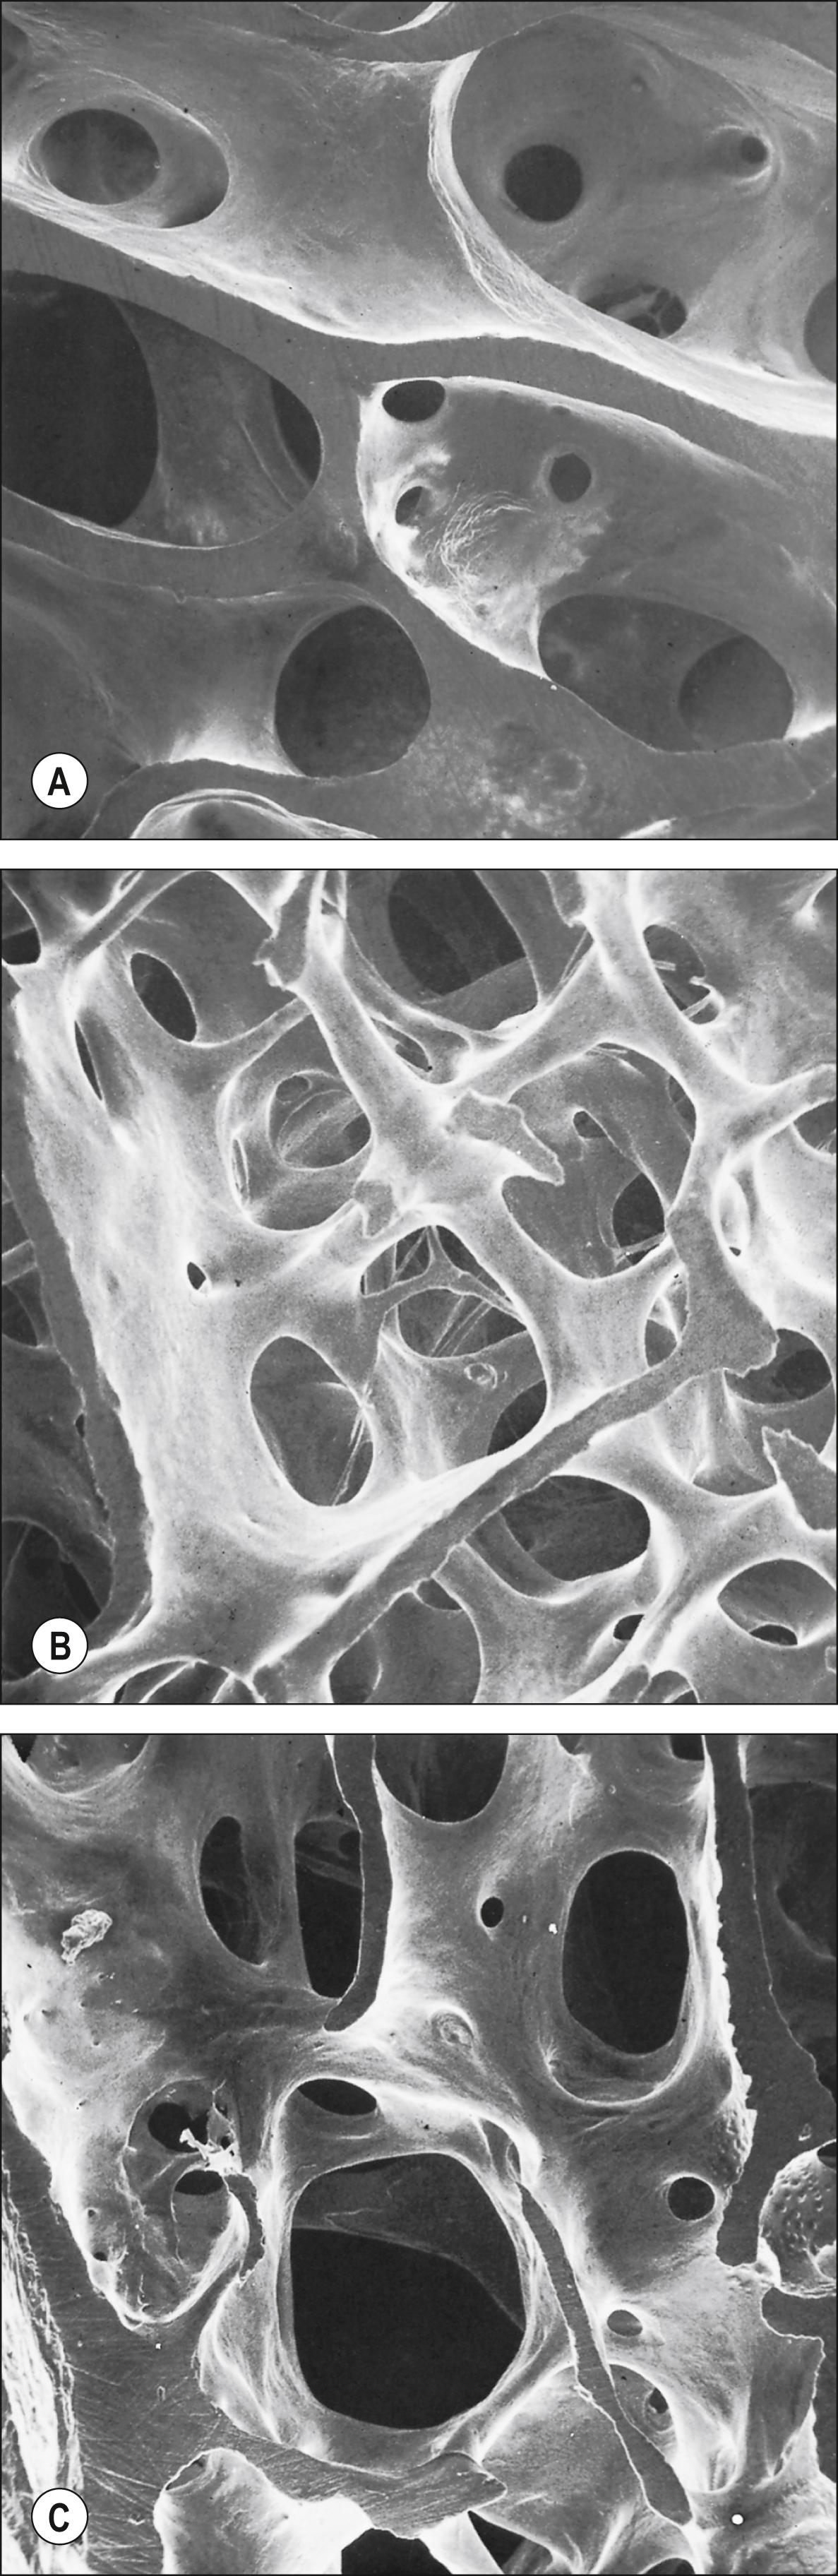

Macroscopically, living bone is white. Its texture is either dense like ivory (compact bone) or honeycombed by large cavities (trabecular, cancellous or spongy bone), where the bony element is reduced to a latticework of bars and plates known collectively as trabeculae ( Figs 5.8 5.9 ). Compact bone is usually limited to the outer shell or cortex of mature bones, where it is important in determining their strength and providing rigid articular surfaces. Cortical thickness and architecture vary between and within bones, and generally decrease with age in adults. Trabecular bone provides support to the cortex while minimizing weight. The presence of a large central medullary canal in long bones also helps to reduce their weight. Spaces within bones provide convenient and secure locations for the storage of haemopoietic tissues and fat. Bone forms a reservoir of metabolic calcium (99% of body calcium is in the bony skeleton) and of phosphate, which is under hormonal and cytokine control.

Fig. 5.9, Trabecular bone at different sites in the proximal part of the same human femur. All fields are shown at the same scale. A , Subcapital part of the neck. B , Greater trochanter. C , Rim of the articular surface of the head. Note the wide variation in thickness, orientation and spacing of the trabeculae.